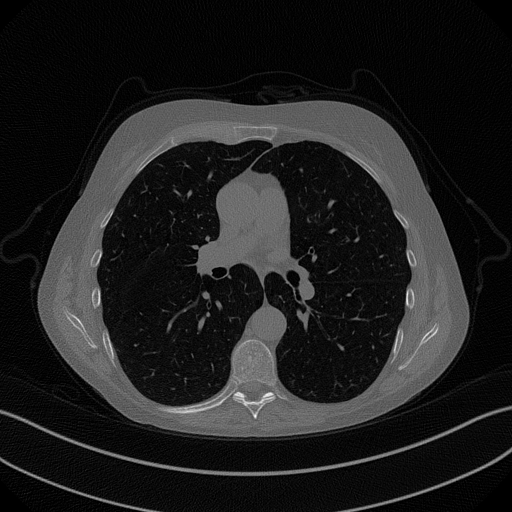

The considered images are pixel reconstructions of human abdomen, computed from full-dose acquisitions. In Figure 2 we depict one image with two zooms-in highlighting areas with different anatomical structures, such as pulmonary details, sections of ribs and low-contrast inter-costal muscles.

In all the experiments reported in 5.1, we have used the images from the data set as ground truth references.

Coherently, we simulate the tomographic projections of the ground truth images, according to a 2D fan-beam geometry, and we add to the sinograms white Gaussian noise with noise level.

To address sparse-view CT reconstructions, we considered two different protocols: the first one is a full angular acquisition with 1-degree spaced projections (we call it in the following); in the second one the scanning trajectory covers degrees and computed only projections (it is labelled as ).

The RIS step executes only iterations, hence we denote as the SGP output which is passed as input to the ING phase.